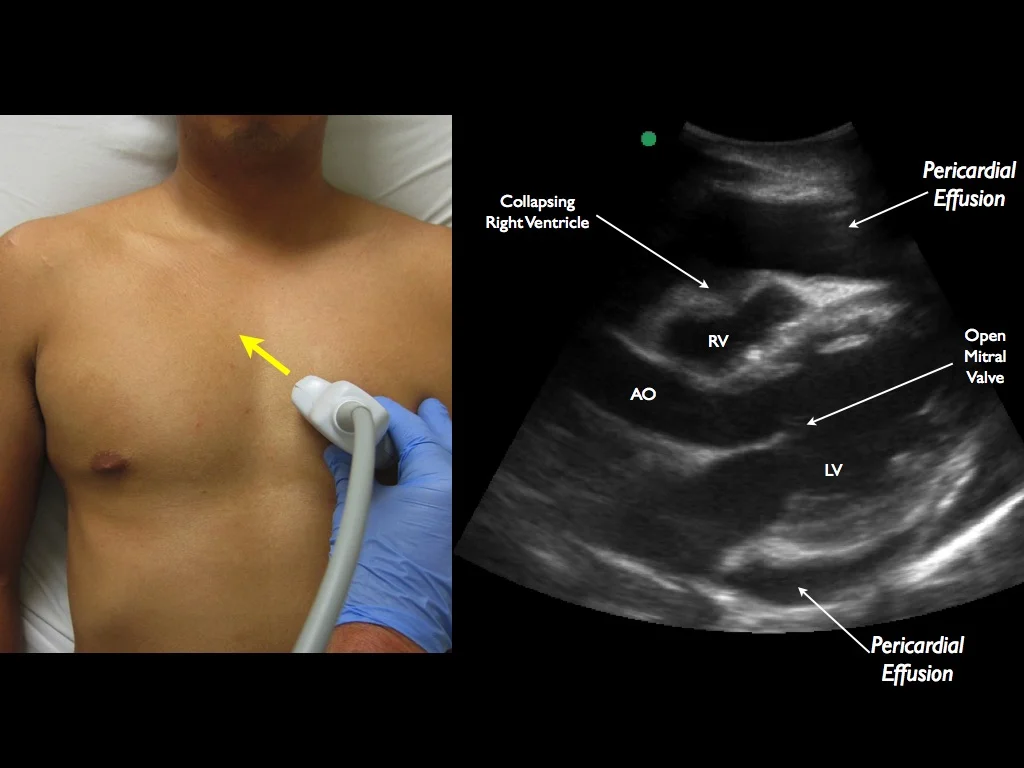

A simplified technique for ultrasound-guided pericardiocentesis.

1) If effusion very midline, locate the mammary arteries with Linear Probe (optional)

2) Confirm reduction in pericardial effusion and IVC collapse